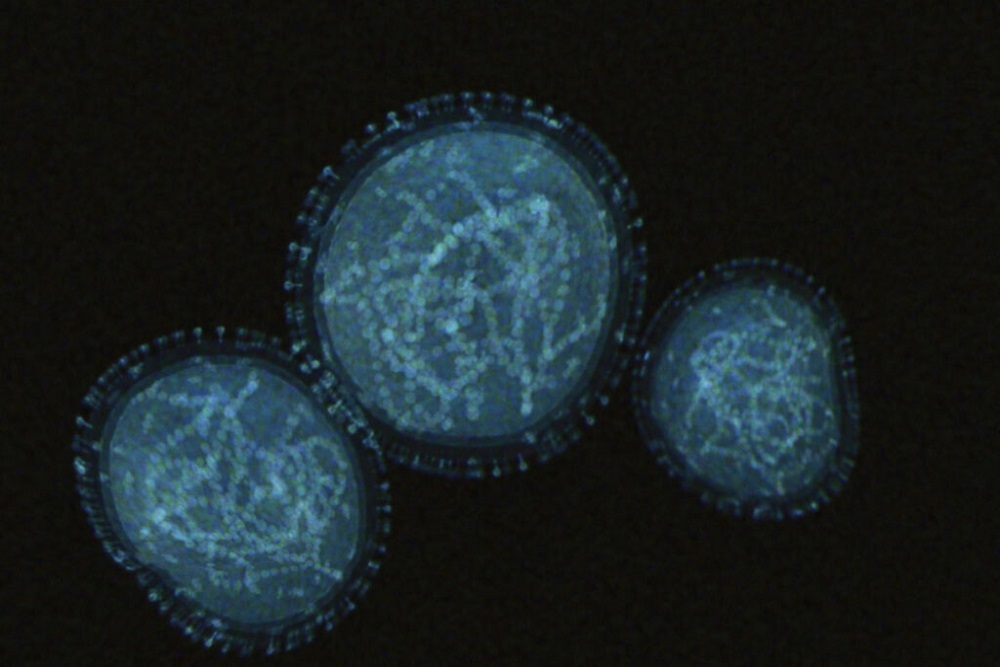

Baltimore county: Monkeypox virus

In anticipation of receiving doses of the Jynneos vaccine used to protect against the monkeypox virus, Baltimore County has launched a survey for high-risk residents interested in being vaccinated.